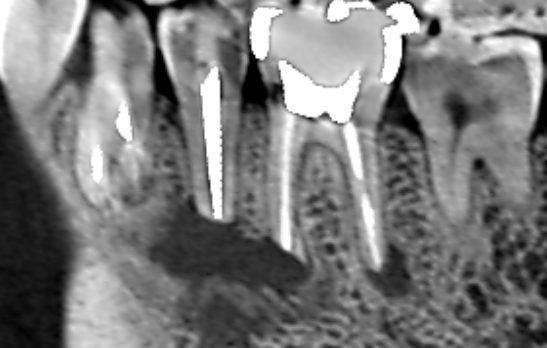

Vol.41 下顎第二小臼歯と下顎第一大臼歯の近心根の両方の根にまたがる膿がみられたケース 2025年12月03日 イスムス清掃・ 下顎第二小臼歯・ 外科的歯内療法後の再発・ 歯槽骨再生・ 精密再根管治療 下顎第二小臼歯と下顎第一大臼歯の近心根の両方の根にまたがる膿があり、口腔外科で外科的歯内療法を受けた… 続きを読む Vol.40 下顎第二大臼歯の遠心根に膿がみられたケース 2025年12月03日 CT診断・ 下顎第二大臼歯・ 歯槽骨再生・ 湾曲根管・ 精密再根管治療 患者さんは特に自覚症状をお持ちでなかったのですが、他の歯の治療でCTを撮影したところ下顎第二大臼歯の… 続きを読む Vol.39 上顎第一大臼歯の近心根に膿がみられたケース 2025年11月13日 上顎第一大臼歯・ 根尖病変・ 根管形態・ 精密再根管治療・ 近心頬側根 上顎第一大臼歯の近心根に膿がみられました。実は、Vol.37、Vol.38、Vol.39は同じ患者さ… 続きを読む Vol.33 歯茎の腫れの原因は隣の歯にあったケース 2025年10月21日 原因歯の特定・ 歯根破折・ 歯槽骨再生・ 歯茎の腫れ・ 精密再根管治療 根管治療を受けているが歯茎の腫れが治らないということで当医院に来院された患者さんです。来院時には… 続きを読む

下顎第二小臼歯と下顎第一大臼歯の近心根の両方の根にまたがる膿があり、口腔外科で外科的歯内療法を受けた…